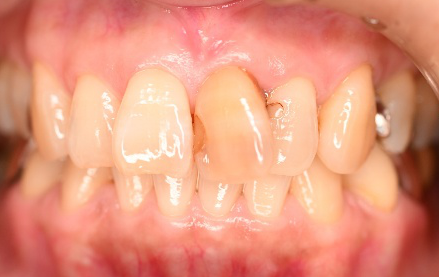

女性Sさん 60代(オールセラミック冠)

主訴

上の前歯2本が動く。何度も取れてはつけ直している。

治療内容

前歯2本が動いていましたが、取れてきていない状態でした。被せ物を削って取り除き、根管治療をし直し、ファイバーコアを入れオールセラミック冠を被せました。

所感

メタルフリーの治療を希望されましたので、ファイバーコアを入れオールセラミック冠を被せました。歯ぎしりが強くあるというお話でしたので、今まで何度も取れている原因の一つに歯ぎしりもあると考え、オールセラミック冠セット時にマウスピースをお渡しし、使ってもらう事にしました。

オールセラミック冠2本:¥104,500×2本=¥209,000(税込)